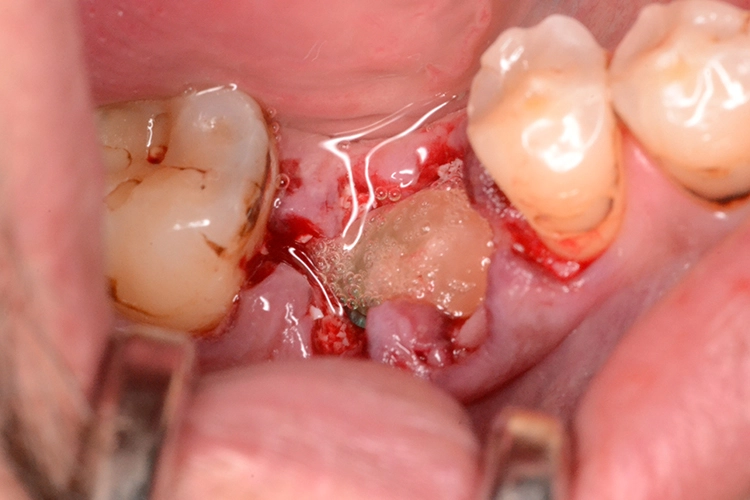

4. Sofortimplantation im Molarengebiet

Dr. Opitz

Aufgrund der Augmentation erfolgte die Freilegung 5 Monate postoperativ. Nach Ausformung des Emergenzprofils (Abb. 4i) erfolgte die definitive prothetische Versorgung durch eine okklusal verschraubte Einzelkrone (Abb. 4j).